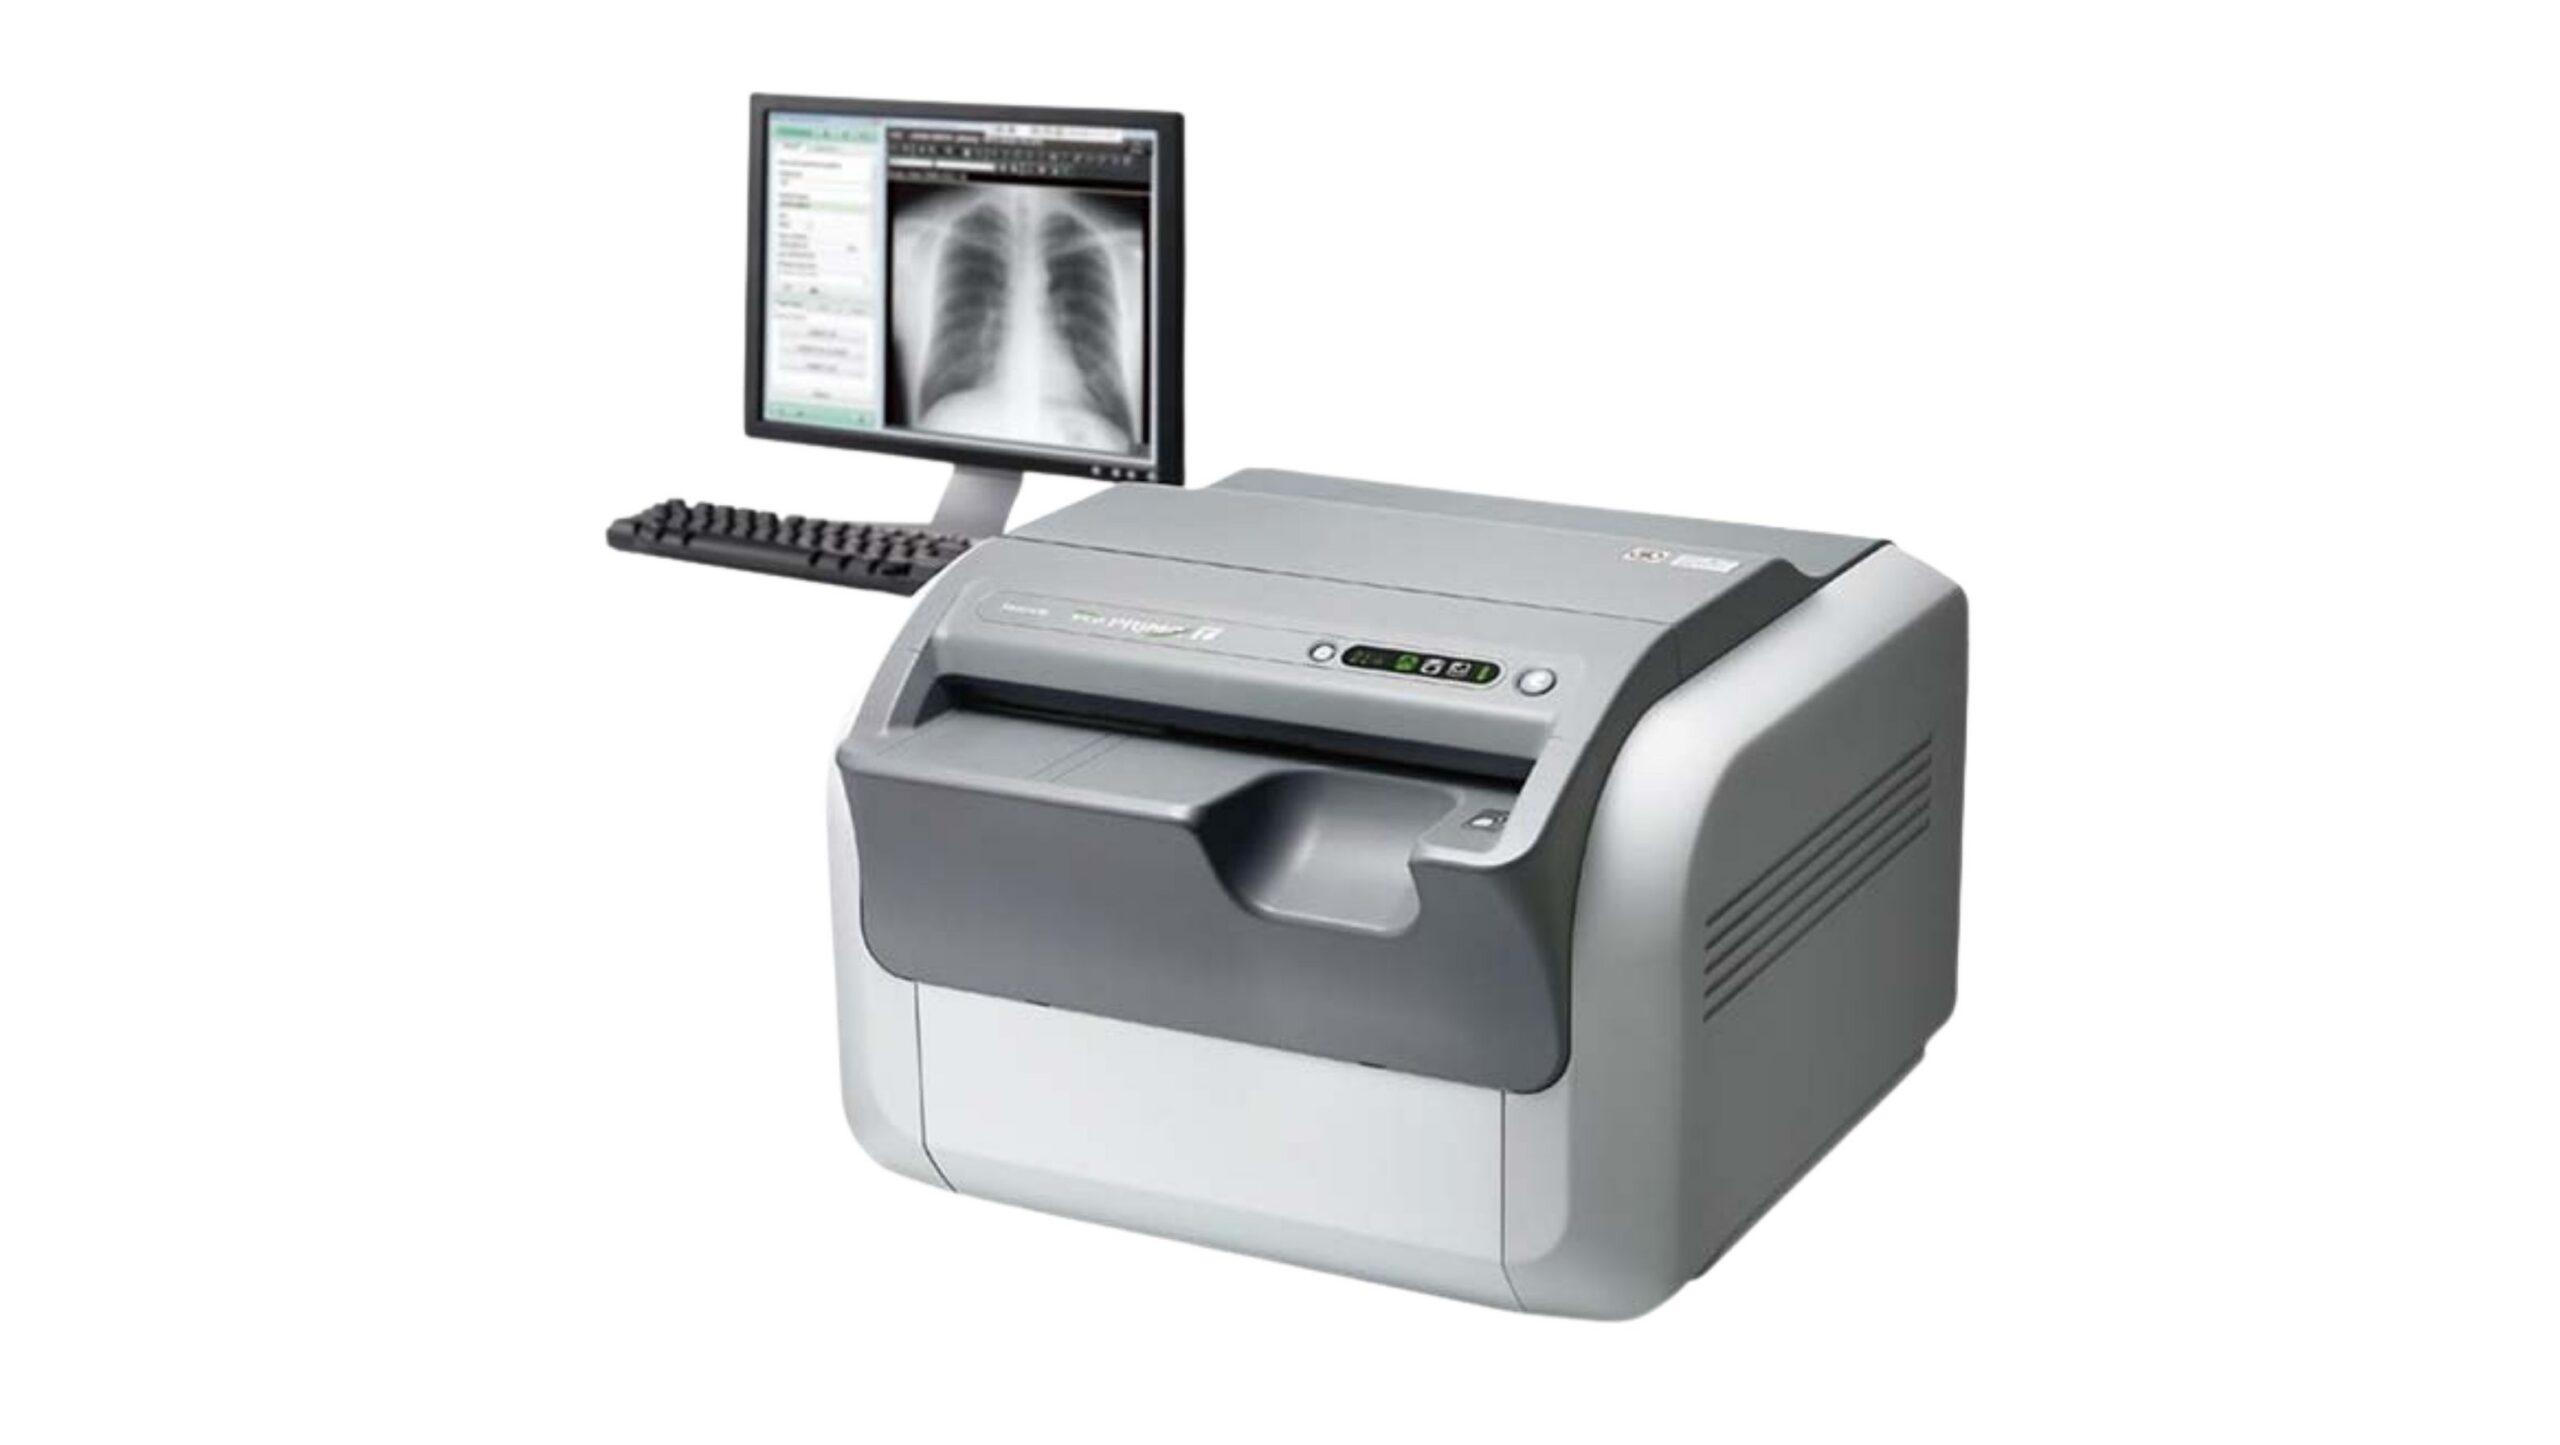

Products

Medem ltd. is a global medical distributor of equipment and consumables.

We provide reliable service for our partners all around the globe. Offering well-known brands such as Fujifilm Healthcare, Carestream Health, Konica Minolta Healthcare and many others. Minimum order quantity is 1 pallet.